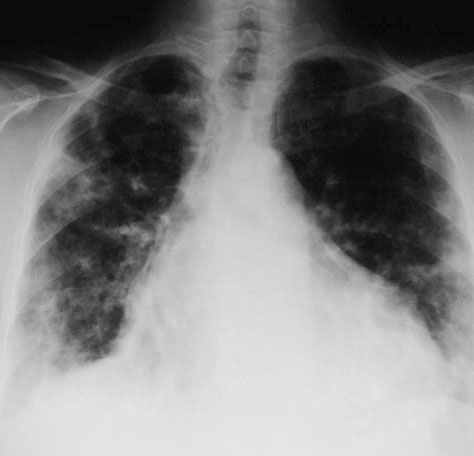

SIGNO DE LAS ALAS DE MARIPOSA

Signo de condensación alveolar bilateral en la radiografía posteroanterior (o anteroposterior) de tórax, propio del edema de pulmón de cualquier causa, aunque también puede verse en neumonías por gérmenes no habituales y hemorragia pulmonar. El signo recibe este nombre por la disposición perihiliar y simétrica de los infiltrados, que respetan la periferia pulmonar.

También se denomina signo de las alas de murciélago, pero está más extendido el término «alas de mariposa», que es, además, más gráfico.